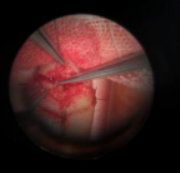

术中探查血管,指尖血管分叉以远断裂,在高倍显微镜下,分别给予吻合两个分支动脉血管及掌侧2根静脉,动脉的血管管径仅有0.2mm,手术难度极大。